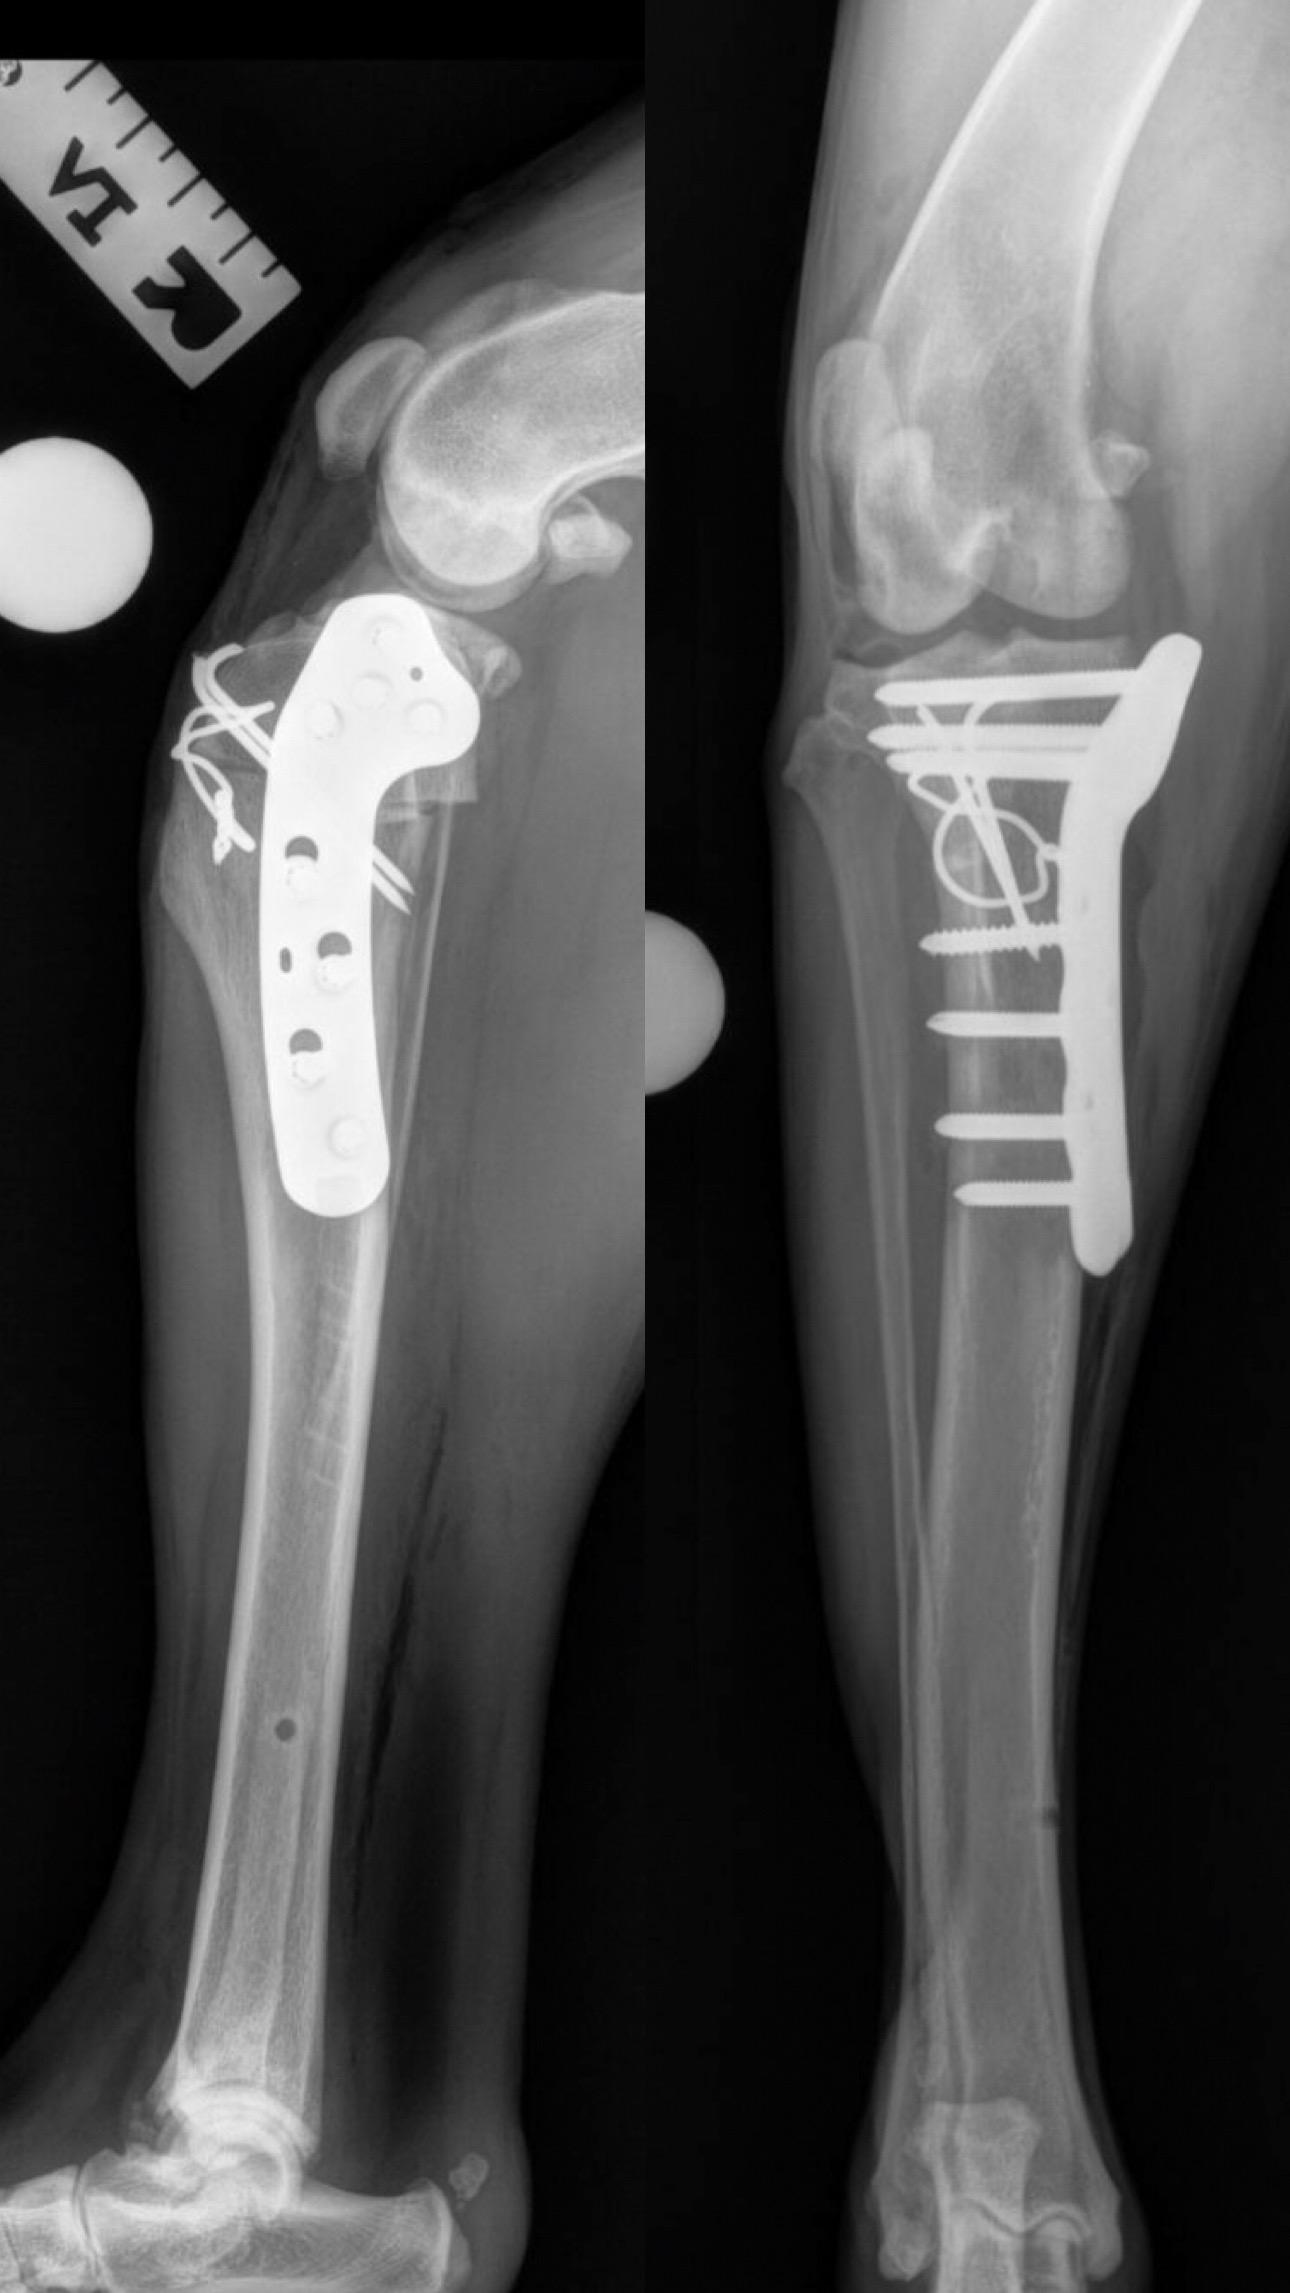

Fracture Repair

We provide surgical fracture repair for many types of broken bones. Treatment plans are individualized based on the location and complexity of the fracture, your pet’s age and size, and overall health.

Large Dog Radius Fracture Before

Large Dog Radius Fracture After #1

Large Dog Radius Fracture After #2